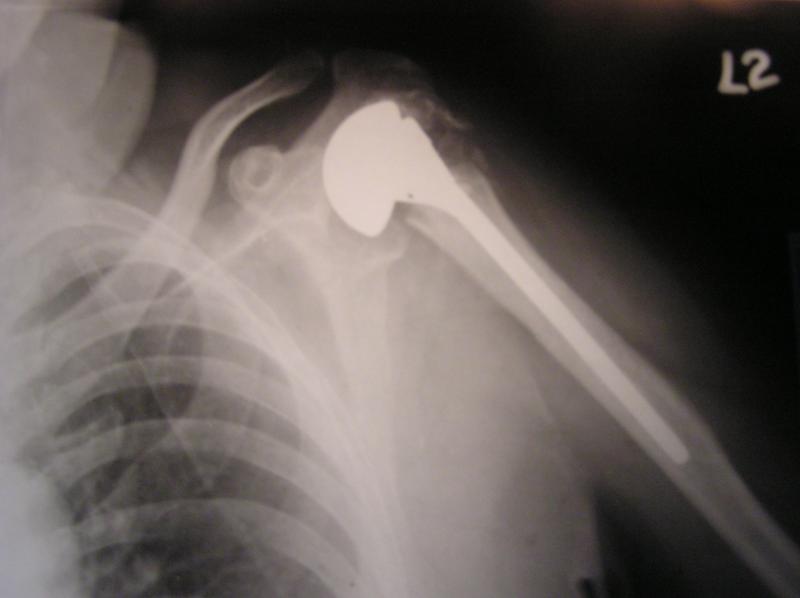

Surface Replacement of hip